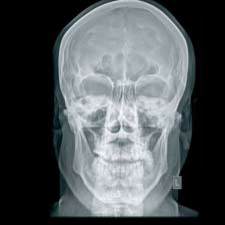

Immagini di alta qualità. Bassi dosaggi. Flusso di lavoro efficiente. DX-G: un livello a parte.